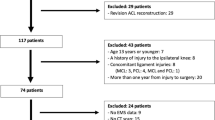

The current study was approved by the ethical committee of Steel Memorial Hirohata Hospital (IRB No. H30-135). Informed consent was obtained from all participants. All methods were performed in accordance with the relevant guidelines and regulations (Declaration of Helsinki). Patients with a unilateral ACL injury treated at our hospital between 2012 and 2018 were eligible for inclusion in this retrospective, case–control study. The inclusion criteria of ACL injury for this study were unilateral ACL injury and age of 16 to 40 years at the time of injury. All patients with ACL injuries had non-contact injuries. We excluded patients with diseases that cause joint inflammation, such as rheumatoid arthritis, with a history of trauma or surgery on the unaffected lower limb, with osteoarthritic (OA) change in either knee or knee flexion contracture on the unaffected side. ACL injuries were diagnosed by manual examination, including the Lachman test, pivot shift test, and anterior drawer test. All ACL injured patients underwent magnetic resonance imaging to confirm ACL tear.

As a control group, the contralateral knee of a patient with a unilateral meniscus injury was used as the normal knee. Patients with discoid meniscal injuries were excluded from this study because of the possibility of morphological tibial abnormalities16.

A total of 100 knees with unaffected side knees of unilateral ACL injured patients (ACL injury group, 53 cases) and normal knees (control group, 47 cases) were evaluated. The participants consisted of 56 males and 44 females with a mean age of 23.6 ± 0.8 years (range 13–40 years).